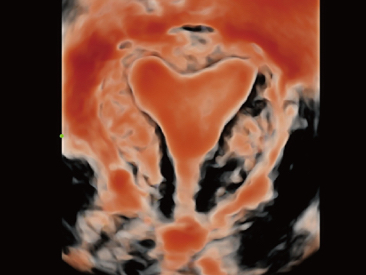

Desde que se fundó la compa?ía, Mindray ha explorado incansablemente nuevas formas de mejorar la confiabilidad del diagnóstico. Con la revolucionaria tecnología de ZONE Sonography?, la nueva plataforma ZST+ de Resona?7 lleva la calidad de la imagen por ecografía a un nivel superior mediante el procesamiento de datos de canal y la adquisición de zona.

Además de la calidad de imagen de primer nivel, Resona?7 también mejora las capacidades de investigación clínica con el revolucionario V?Flow para la evaluación hemodinámica vascular y con la adquisición de planos más inteligente a partir de conjuntos de datos 3D para el diagnóstico del SNC fetal. Al combinar el funcionamiento multitáctil basado en gestos más intuitivo y todas las características clínicas esenciales, Resona?7 realmente lidera las novedades en innovación de ecografías.